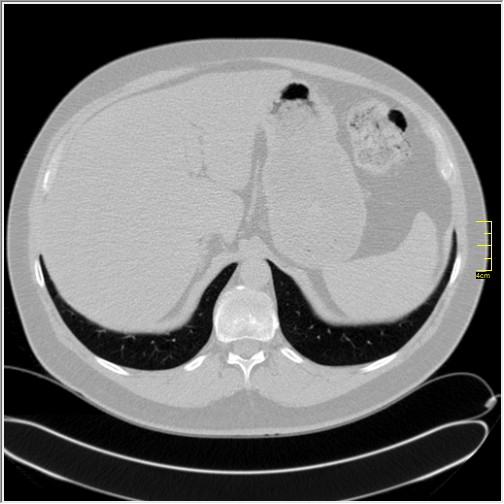

Četiri dana kasnije. Isti pacijent dolazi sa istim pulmologom. Situacija je sada sasvim drugačija. Temperatura 39.5 C. Saturacija 92. Laboratorija daleko gora. Uradim CT pluća. Ovo je izašlo.

Severity score 15/25. Pacijent je upućen na bolničko lečenje.

Ono što zbunjuje, a to se ponavlja zadnjih 10 dana, je da fibroza nastupa u progresivnoj fazi, znači na početku bolesti. Toga nije bilo do sada. Sledećih dana ću o tome.

Ovo je samo 4 dana. Od zdravlja do teške bolesti. Pacijent je 45 godina starosti, očigledno nije povećane težine, kaže za sebe da je bio sportista. U anamnezi nije naveo nikakve bitne bolesti.